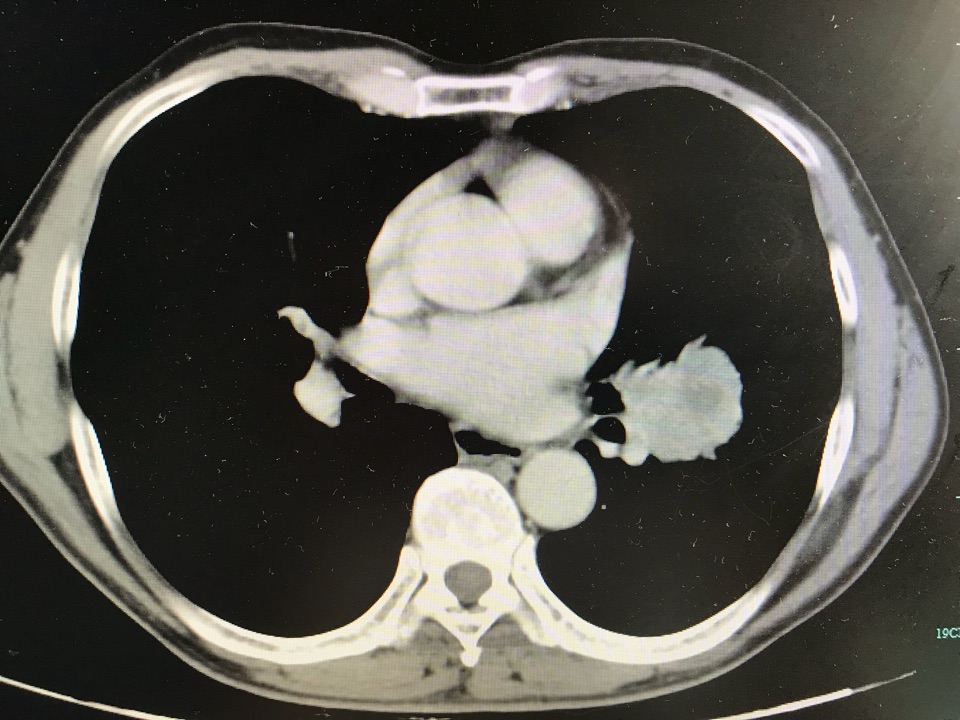

顺利切除巨大复杂左下肺中央型鳞癌!